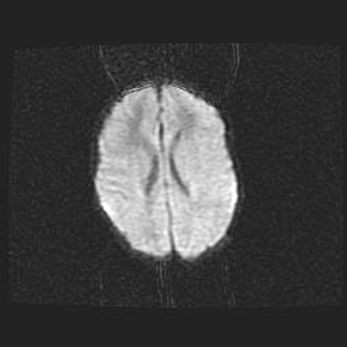

Церебральная ишемия II.

Возраст: 5 дней

Вес: 3400 г

Пол: женский

Окружность головы: 35 см

Срок гестации: 39 недель

Церебральная ишемия – это заболевание, характеризующееся недостаточностью (гипоксией) либо полным прекращением (аноксией) снабжения мозга кислородом по причине закупорки одного или нескольких сосудов. Это приводит к  что метаболическим расстройствам различной степени тяжести в тканях головного мозга, развитию коагуляционных некрозов и гибели нейронов.